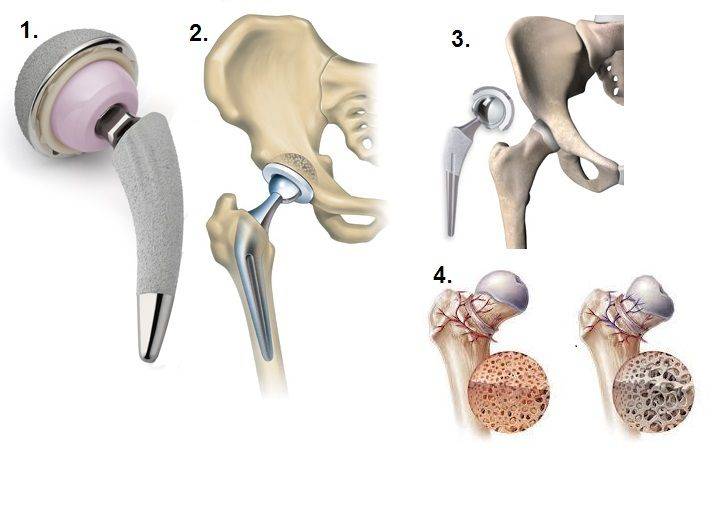

Эндопротезирование тазобедренного сустава: фото и схемы